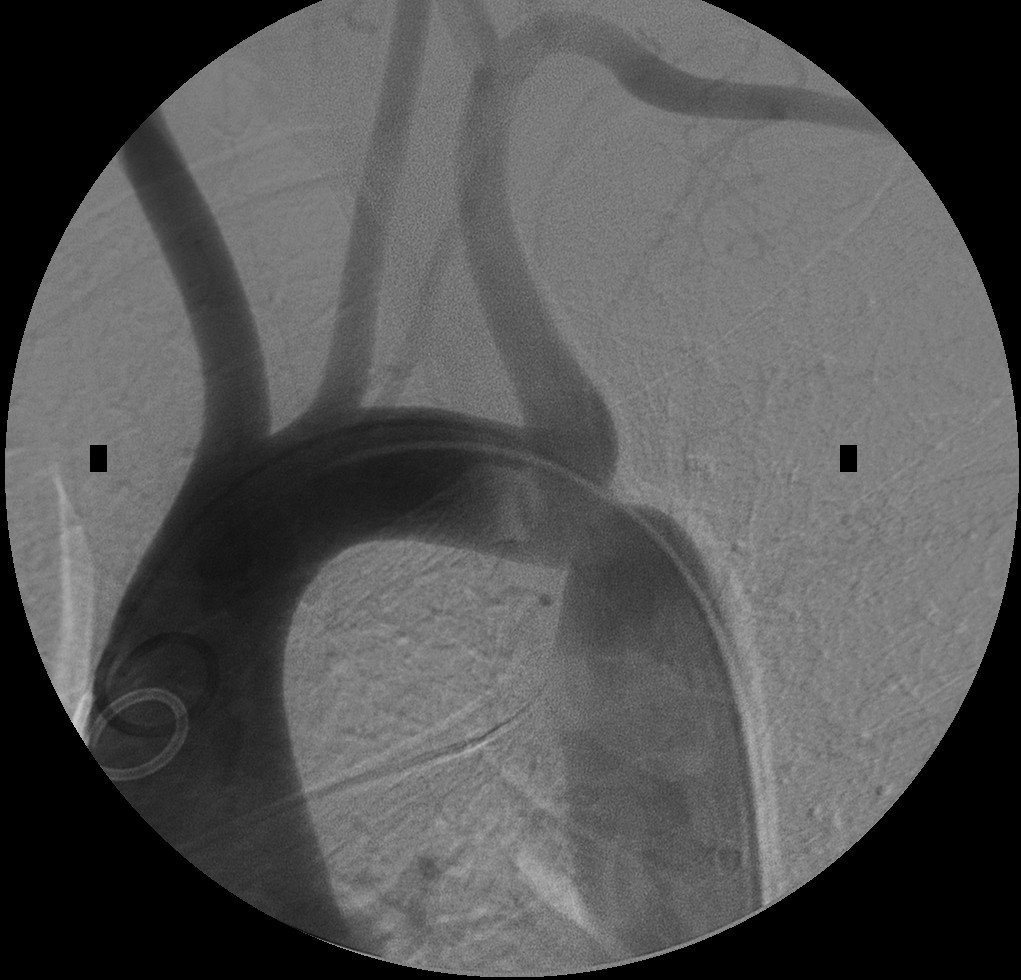

- Эхокардиография. Этот метод является основным для диагностики гипертрофии левого предсердия. Визуализация позволяет врачам определить наличие дефектов и стадию их развития. Эхо-КГ помогает выявить причины патологии, такие как пороки аорты и сердечных клапанов.

В последние годы наблюдается рост интереса к неинвазивным методам диагностики гипертрофии левого предсердия. Ультразвуковая эхокардиография остается золотым стандартом, однако новые технологии, такие как магнитно-резонансная томография (МРТ) и компьютерная томография (КТ), предлагают более детальную визуализацию и оценку структуры сердца. Эти методы позволяют не только диагностировать ГЛП, но и отслеживать динамику изменений в размерах предсердия в процессе лечения.